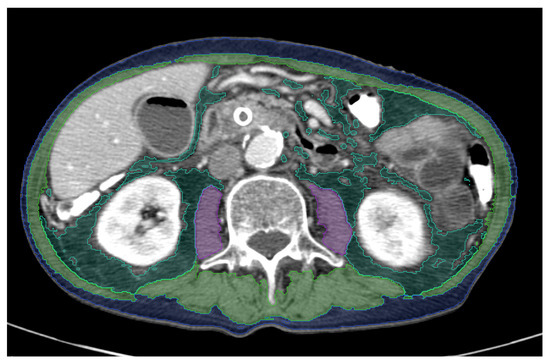

Influence of Baseline CT Body Composition Parameters on Survival in Patients with Pancreatic Adenocarcinoma

Pancreatic cancer is the seventh leading cause of cancer death in both sexes. The aim of this study is to analyze baseline CT body composition using artificial intelligence to identify possible imaging predictors of survival. We retrospectively included 103 patients. First, the presence [...] Read more.

Pancreatic cancer is the seventh leading cause of cancer death in both sexes. The aim of this study is to analyze baseline CT body composition using artificial intelligence to identify possible imaging predictors of survival. We retrospectively included 103 patients. First, the presence of surgical treatment and cut-off values for sarcopenia and obesity served as independent variates. Second, the presence of surgery, subcutaneous adipose tissue (SAT), visceral adipose tissue (VAT), and skeletal muscle index (SMI) served as independent variates. Cox regression analysis was performed for 1-year, 2-year, and 3-year survival. Possible differences between patients undergoing surgical versus nonsurgical treatment were analyzed. Presence of surgery significantly predicted 1-year, 2-year, and 3-year survival (p = 0.01, <0.001, and <0.001, respectively). Across the follow-up periods of 1-year, 2-year, and 3-year survival, the presence of sarcopenia became an equally important predictor of survival (p = 0.25, 0.07, and <0.001, respectively). Additionally, increased VAT predicted 2-year and 3-year survival (p = 0.02 and 0.04, respectively). The impact of sarcopenia on 3-year survival was higher in the surgical treatment group (p = 0.02 and odds ratio = 2.57) compared with the nonsurgical treatment group (p = 0.04 and odds ratio = 1.92). Fittingly, a lower SMI significantly affected 3-year survival only in patients who underwent surgery (p = 0.02). Especially if surgery is performed, AI-derived sarcopenia and reduced muscle mass are unfavorable imaging predictors. Full article